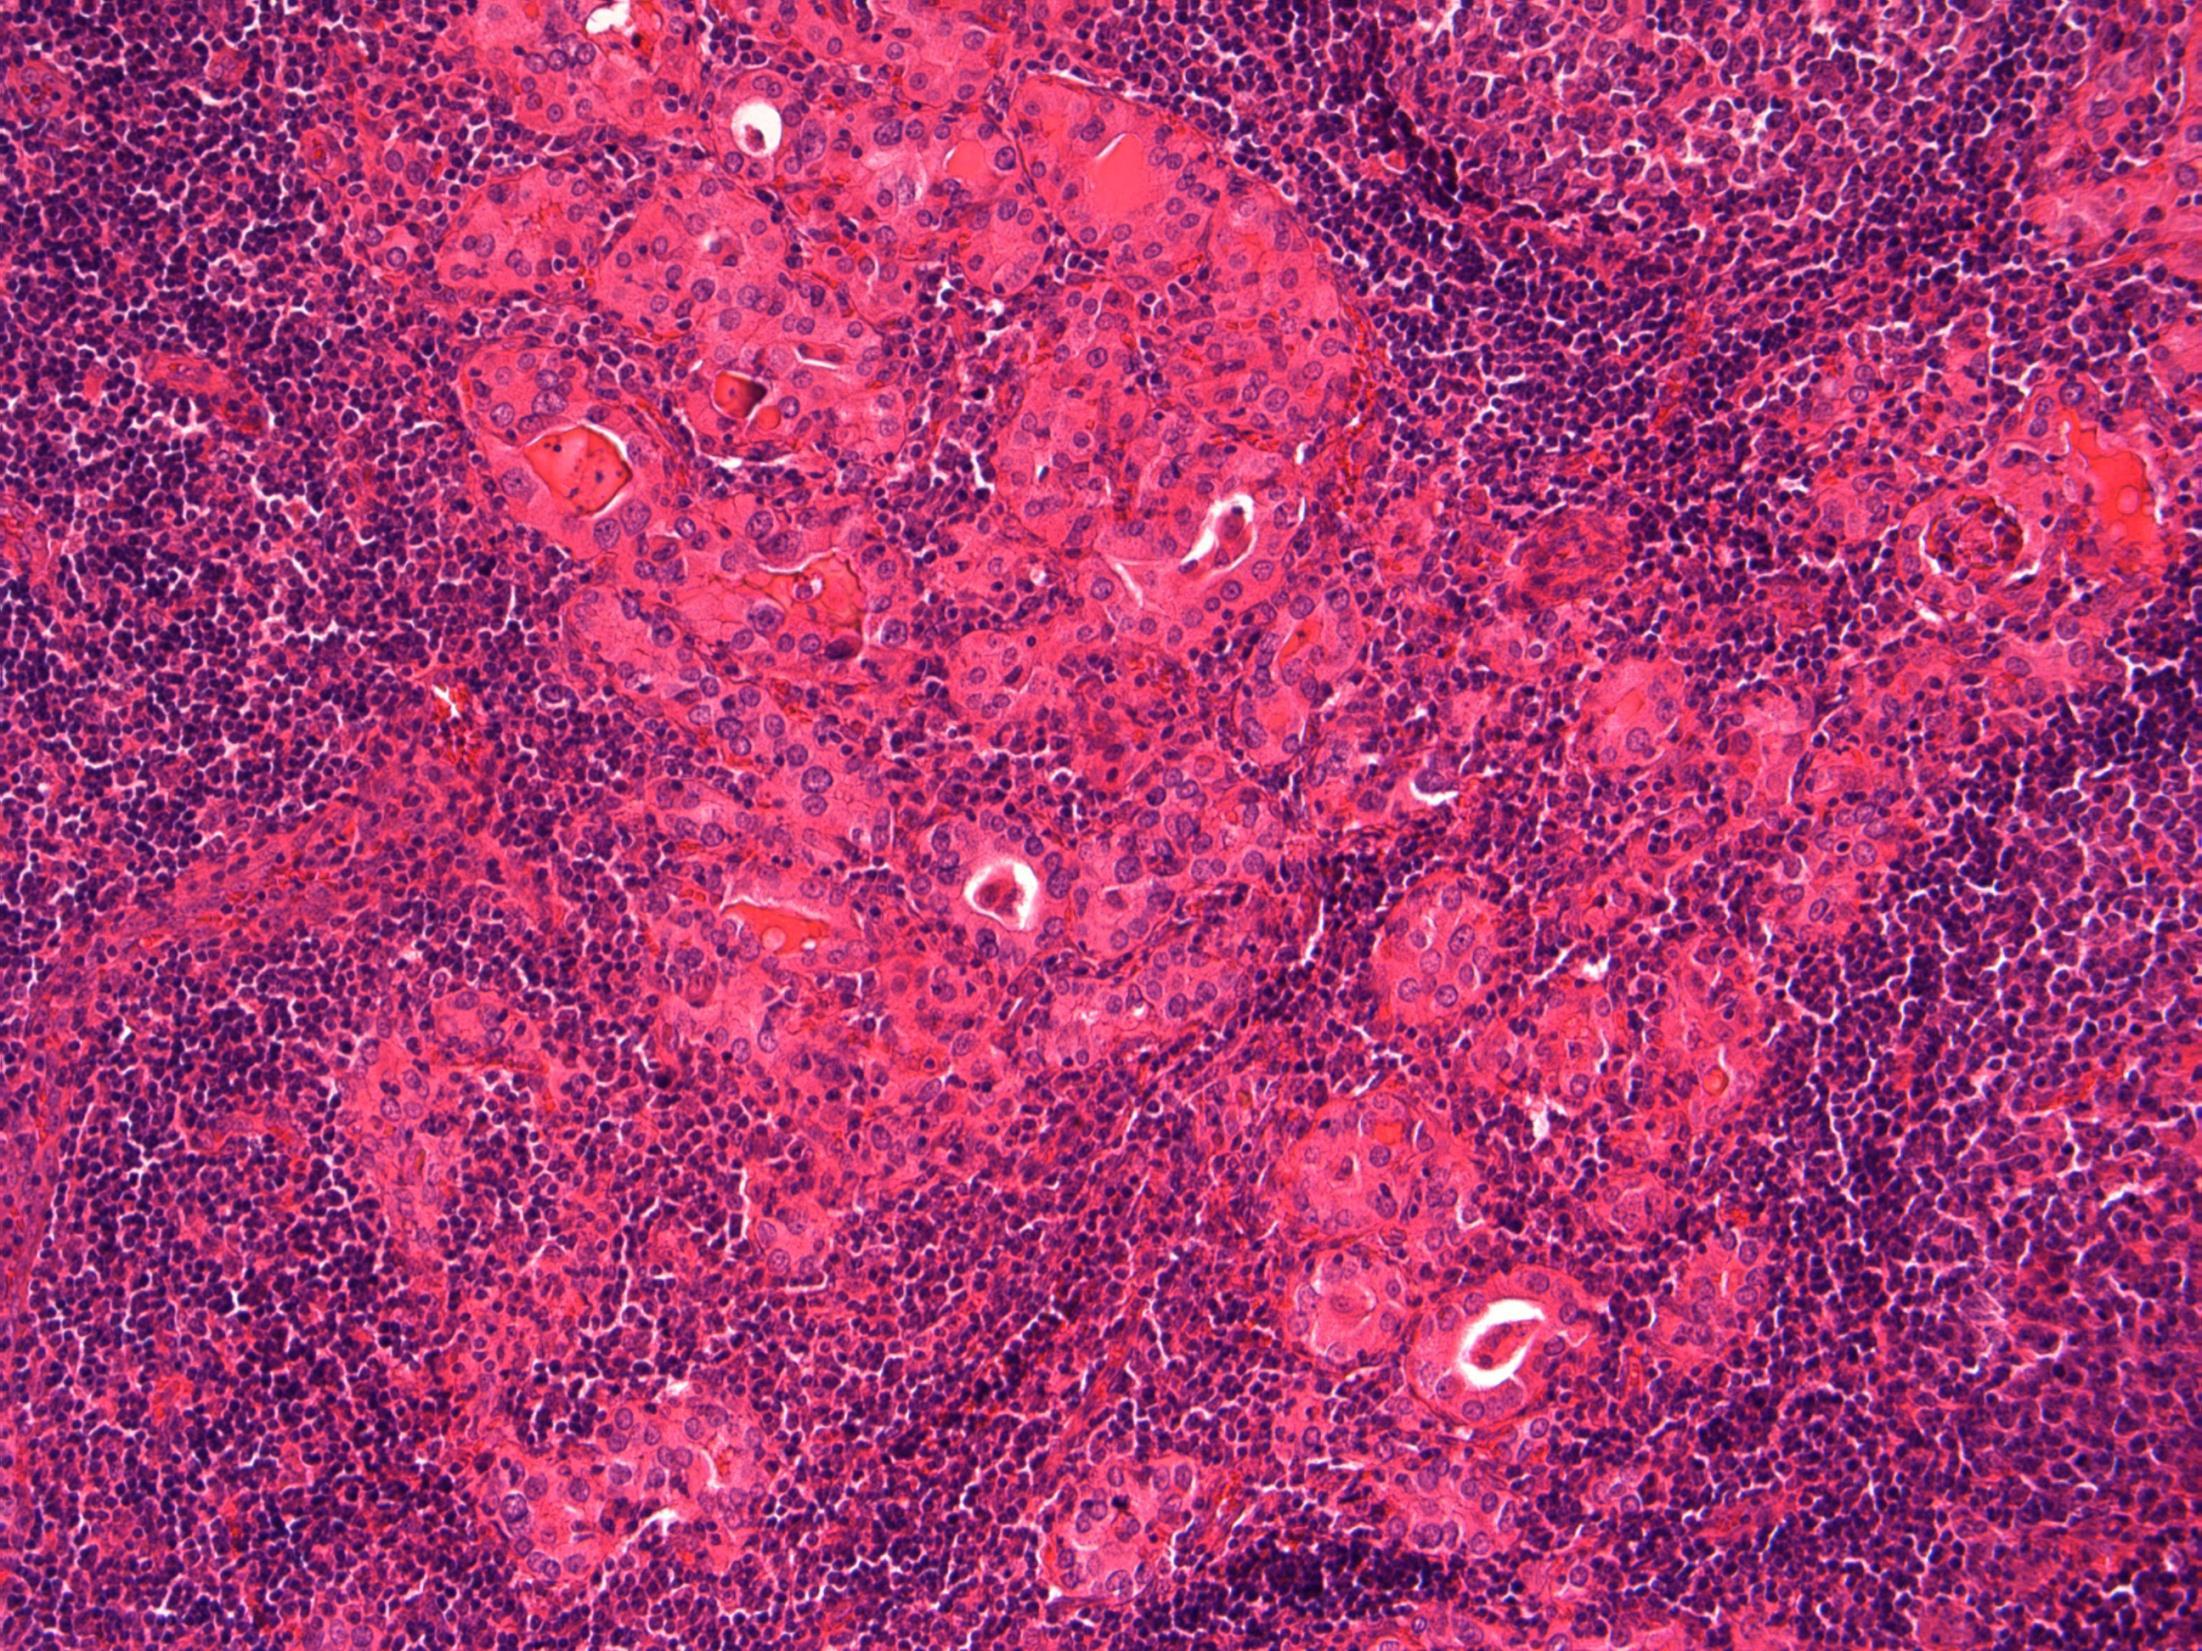

G3 (high-grade) TCC with small cell carcinoma component

Description: Biphasic malignant tumour. High grade large epithelial cell component and high grade small round blue cell tumour component. CIS also seen.

Favoured Diagnosis: G3 (high-grade) TCC with small cell carcinoma component. Plan: Correlate with urine cytology/ previous biopsies. IHC: TCC= AE1/3+, p63+, small cell ca = AE1/3 dot +, CD56+, synapto +. Look for invasion into lamina propria and muscle (staging).

Comments: • Small cell carcinoma is frequently admixed with TCC, SCC or adenocarcinoma of bladder • >90% muscle invasive and metastases common, poor prognosis. • Responds to chemotherapy (cisplatin based) • Differential Diagnosis of pure small cell carcinoma: – Poorly-differentiated urothelial carcinoma – Metastatic small cell carcinoma from other site eg lung – Lymphoma – Alveolar rhabdomyosarcoma – Inflammation (in a crushed, cauterised, superficial or scant specimen)